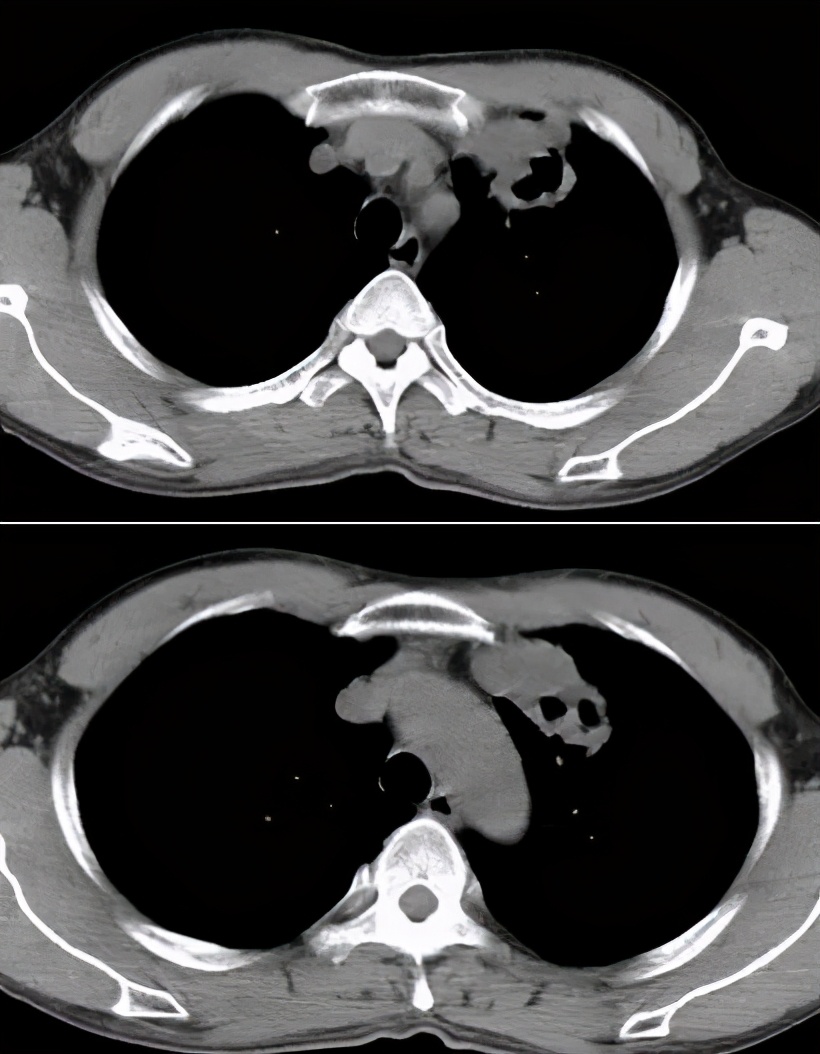

对于ICH的肺结核病影像表现,我与大家分享一些病例

病例1:

68岁,男性,2017年1月入院。主诉:反复发热2月,右侧胸隐痛;现病史:胸部CT示双肺散在炎症,抗感染治疗(头孢菌素、呼吸喹诺酮)后有吸收;但症状反复。

寻常型天疱疮,长期美卓乐、硫唑嘌呤治疗;类固醇性糖尿病。

CRP 196↑ mg/L;白细胞计数 9.12 ×10^9/L 中性粒细胞% 98.2;反复痰找抗酸杆菌(-)。

右侧胸腔穿刺,抽得脓性胸水,胸水涂片见抗酸杆菌4+。

图:2017-1 胸部CT:左肺上叶后段团片影,较前片有所减小;两肺多发炎症,较前片部分吸收;右侧胸膜增厚、胸腔积液,较前片有所增多。